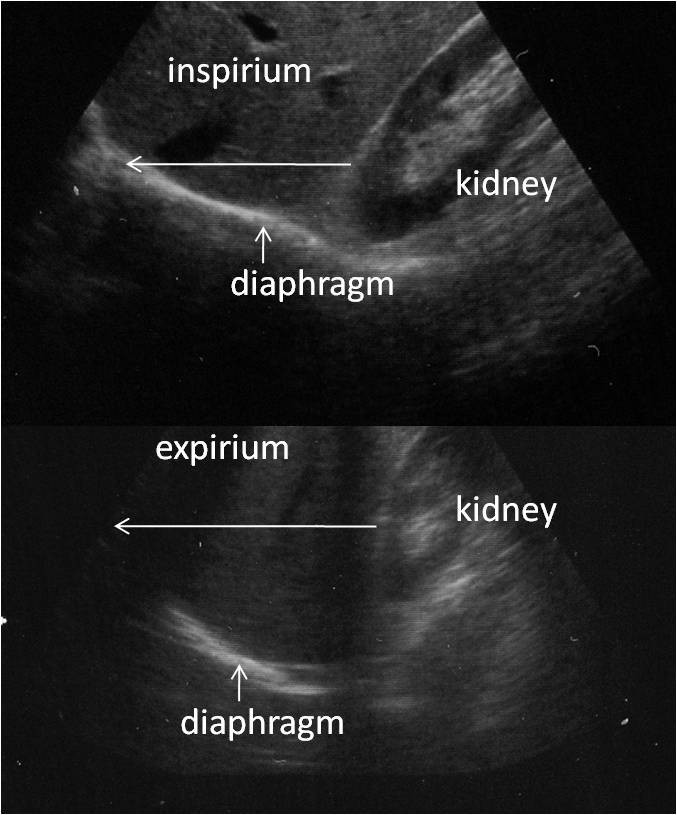

From cardiothoracicsurgery.biomedcentral.com

Diaphragm motion and lung function prediction in patients operated for Diaphragm Function Lungs The diaphragm is a muscle that helps you breathe. The diaphragm is the most important muscle of respiration, [ 3 ] and separates the thoracic cavity, containing the heart and lungs, from the. It sits under your lungs and separates your chest cavity from your abdomen. Your heart, lungs, and the upper part of your esophagus (food pipe) are in. Diaphragm Function Lungs.